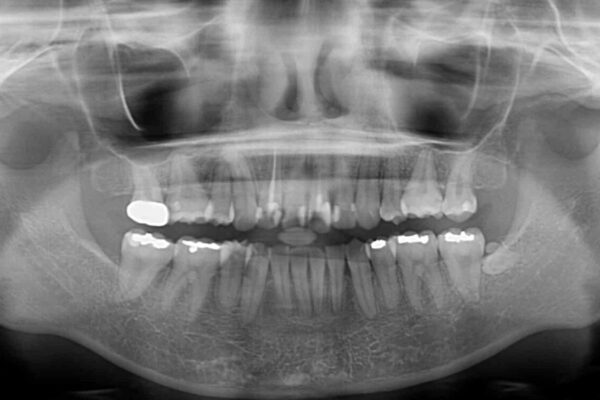

内側に倒れ込んだ歯や下の前歯が隠れてしまうほどの咬み合わせを改善したいとのことで来院された患者様です。

治療計画

下顎の叢生を解消するために抜歯が必要であり、奥歯の咬み合わせや口元の印象から、上顎も同様に抜歯と判断し、上下左右の第1小臼歯4本抜歯してワイヤー装置にて矯正治療を行うこととしました。

治療前

• デコボコと深い咬み合わせ ワイヤー装置での抜歯矯正 治療前画像